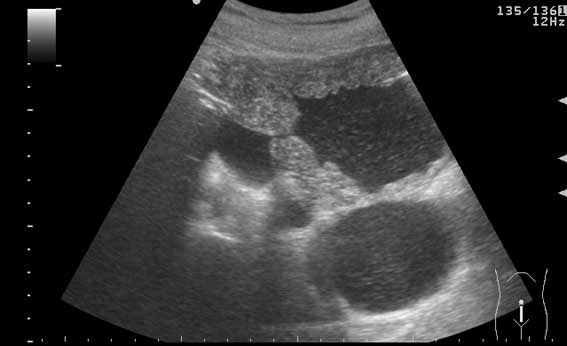

УЗИ мочевого пузыря у пожилого мужчины выявлены следующие изменения.

Signs of chronic urinary retention; evident thickening of the urinary bladder mucosa; large diverticulas. Residual volume evlaluation required; full prostatic assessment is recommended.

But really there are two ones on these pictures.Dr.Mario писал(а):I agree with previous post (Dr. Uzgraph); but there may be much more of them.

неравномерное утолщение стенок мочевого пузыря,признаки застоя в мочевом пузыре,расширенные дистальные отделы мочеточников,на первом снимке-дивертикул?слева,уввеличенная отечная простата

Все верно, за исключением того что простаты на картинках нет. Здорово, что Вы заметили расширение мочеточников. Есть также воздух в МП после цистоскопии.besliu писал(а):неравномерное утолщение стенок мочевого пузыря,признаки застоя в мочевом пузыре,расширенные дистальные отделы мочеточников,на первом снимке-дивертикул?слева,уввеличенная отечная простата